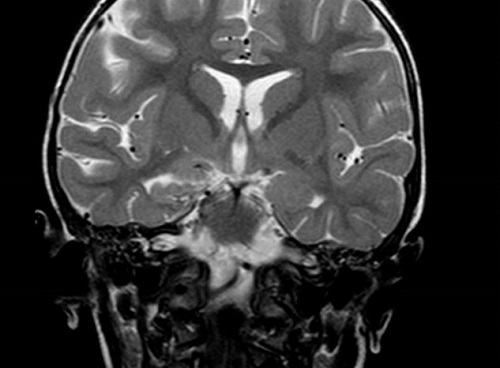

A los 15 días de ingreso, se repite el estudio de imagen, que muestra una disminución significativa de las lesiones descritas en el troncoencéfalo, el hipocampo y el tálamo, con desaparición de la afectación del pálido y tracto óptico retroquiasmático derecho, hallazgos compatibles con encefalitis viral evolucionada.